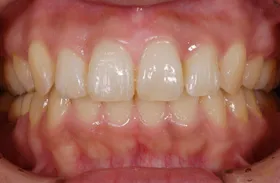

■治療前:奥歯が無いため噛み合わせが深く下の歯が全く見えない

噛み合わせが低いため全体的に歯が削れている

■治療後:下顎 左下5・6番、右下4・6番にインプラント治療

その他の歯に補綴治療をしたことにより、奥歯もしっかりと咬むことができ、奥歯ができたことにより噛み合わせも上がって下の歯も見えるようになり、審美的にも改善された

| 主訴 | 歯科治療をしても歯がすぐに欠けてしまう 奥歯が無いため、奥歯で咬めない |

| 治療方法 | インプラント治療 + 補綴治療 |

| 治療期間 | 約1年 |

| 通院回数等 | 約20回 |

| 費用 | 約250万円(税込) |

| リスク・副作用 | 術後の腫れ・痛み |